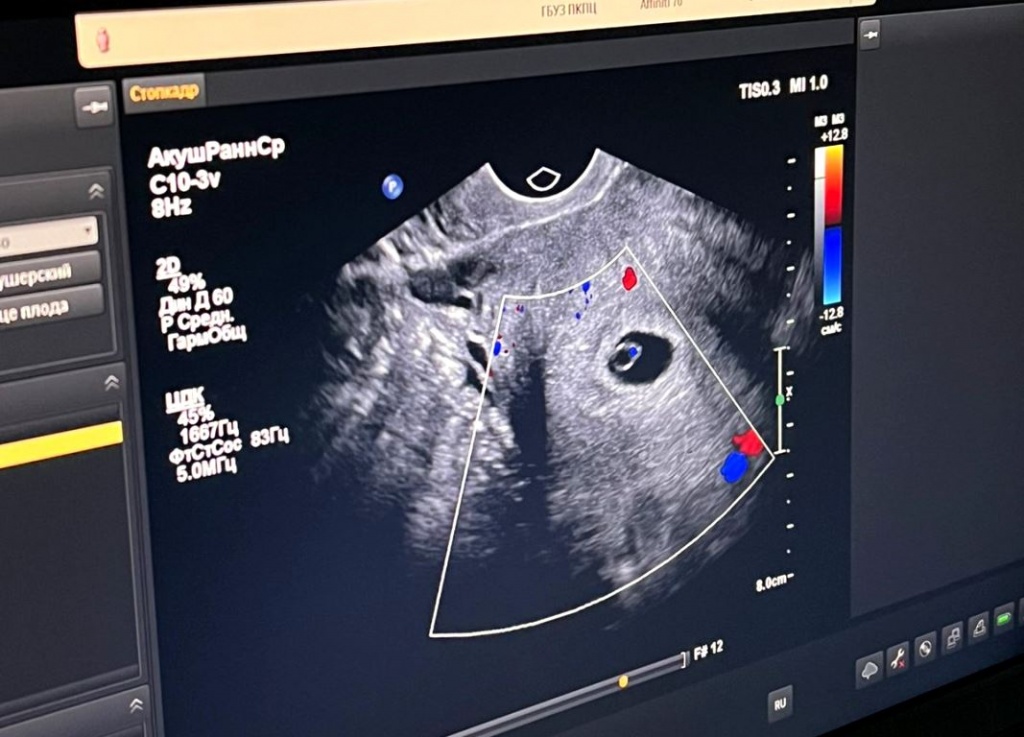

С каждым днём все больше приморских семей исполняют свою главную мечту – стать родителями. Только с начала года врачи Приморского краевого перинатального центра помогли исполнить заветное желание 160 приморским семьям, проведя бесплатные процедуры ЭКО.

Отделение ЭКО Приморского краевого перинатального центра распахнуло свои двери весной прошлого года, и уже в канун Нового года первые семьи, прошедшие процедуру, празднование рождение своих малышей. Сегодня здесь с каждым днём всё больше и больше семей слышат долгожданную фразу врачей «Поздравляем! Вы беременны».